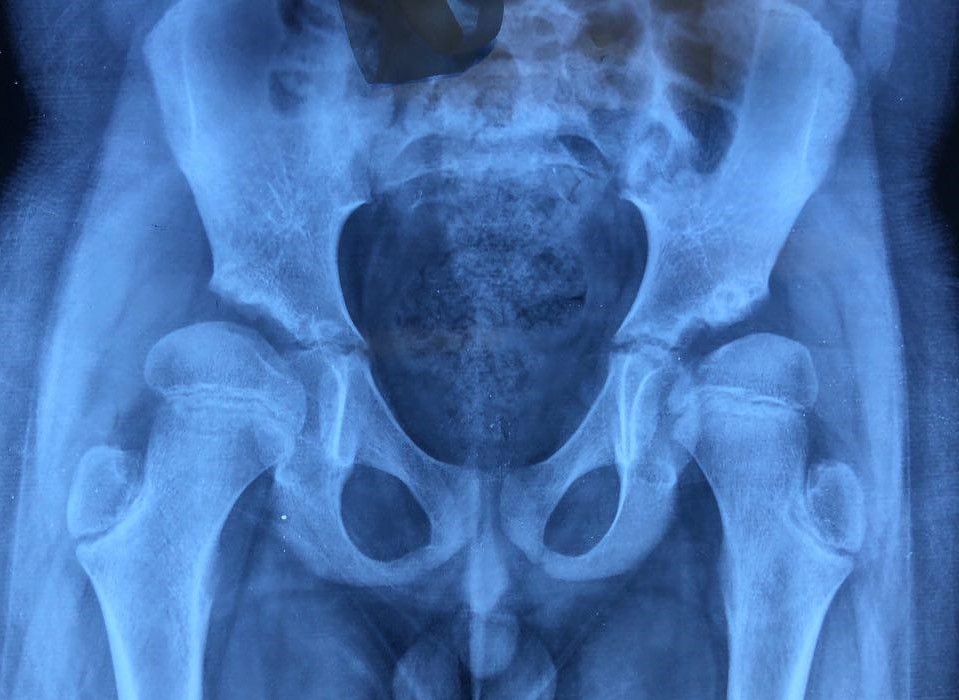

High Acetabular Fossa and Downsloping Sourcil

A high acetabular fossa (medial dysplasia) or a downsloping sourcil (reverse sourcil angle) can load a normally placed fovea against the usually non-weight-bearing acetabular fossa, crushing the ligamentum teres and causing medial osteoarthritis of the hip. Treatment is reverse periacetabular osteotomy before arthritis sets in.

Foveal loading from high acetabular fossa and downsloping sourcil causing medial osteoarthritis

Foveal loading from high acetabular fossa and downsloping sourcil causing medial osteoarthritis.